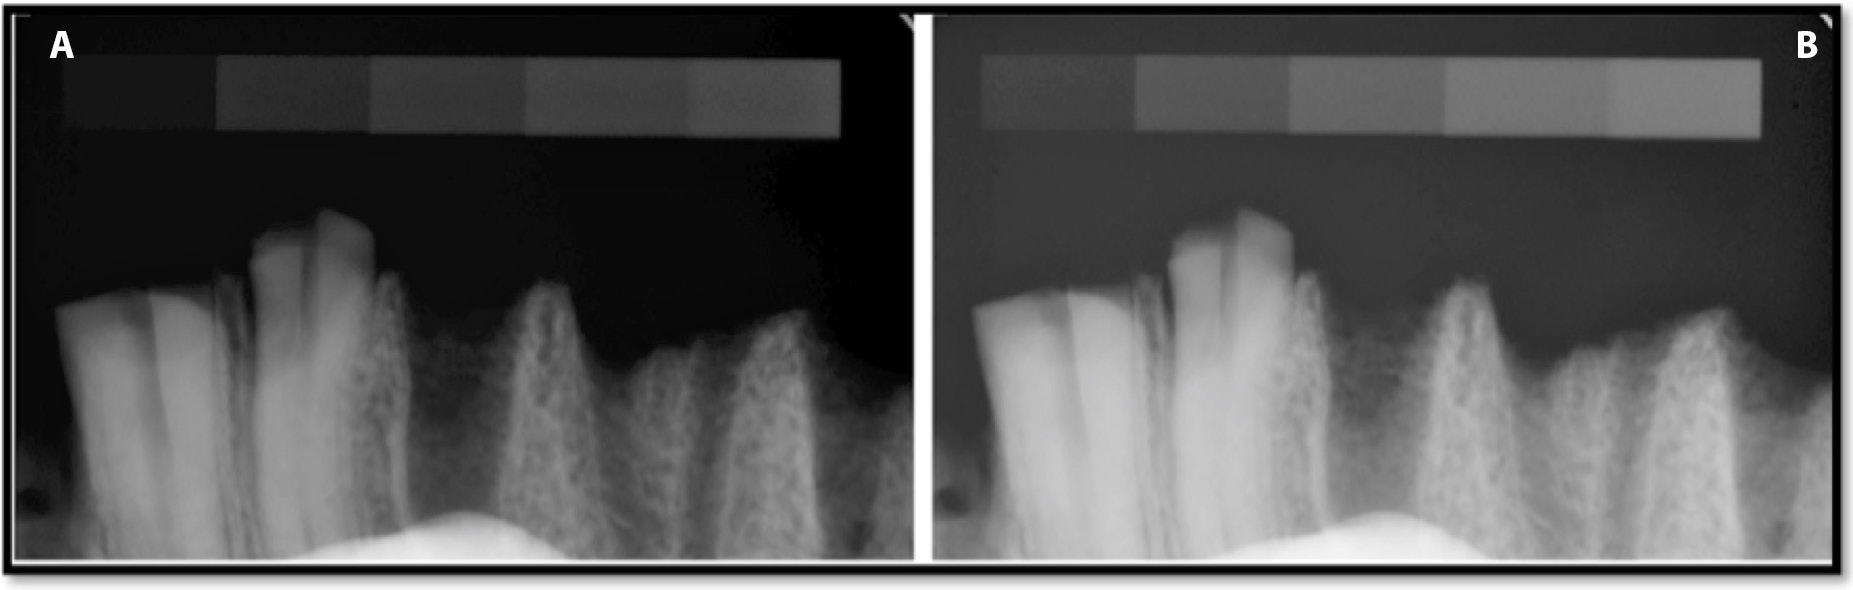

The recorded optical density values of the Group C radiograms captured at exposure times of 0.05 s and 0.125 s and the original images are presented in Table 4 and Figure 11. The Group C radiograph of bone specimen captured at an exposure time of 0.125 s is presented in Figure 12. The analysis of the Group C images (export without optimization) revealed that not applying the automated adjustment function after file import yielded an increase in the optical density values of the radiographs of all the phantom degrees over the original images (enhanced with the optimization algorithm). The increase was independent of exposure time (at 0.05 s the value changed from 80.2% to 4.4% and at 0.125 s from 82.9% to 4.7%). However, activating this function (after import) provided an optical density almost identical to the original radiographs of all phantom degrees at both exposure times. Similarly Group C radiographs of the bone samples appears identical to those of Group A. (Figure 7 and 11).